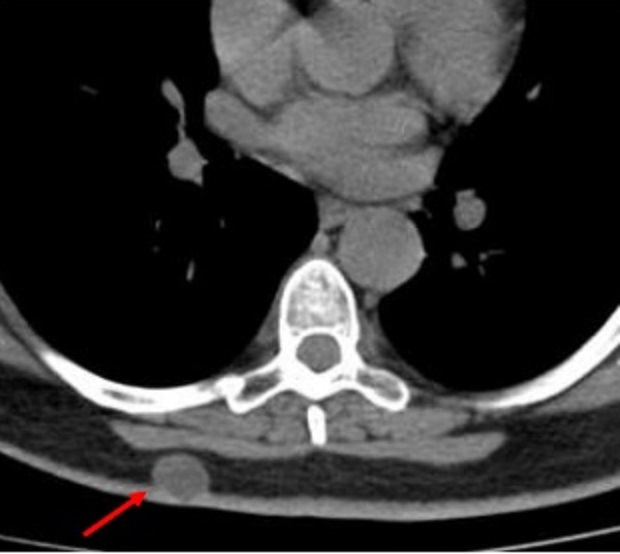

Espect metastatique de

tumefaction de la paroi thoracique droit et de

lyse de destruction osseuse correspondence du

côté droit d'une tumeur metastatique ( fleche rouge

) à origine de cancer pulmonaire ++ droit . Image

radiologique TDM en coupe axial |